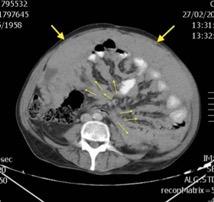

Pancreatitis aguda.

Lesiones infradiafragmáticas

Pancreatitis. (lado izquierdo.68%)

Neoplasia gástrica/pancreática.

Ortiz-Morales CM et al. Radiology of acute pancreatitis today: the Atlanta classification and the current role of imaging in its diagnosis and treatment . Radiologia (Engl Ed) . 2019

Dahnert 2017 Pancreatitis aguda